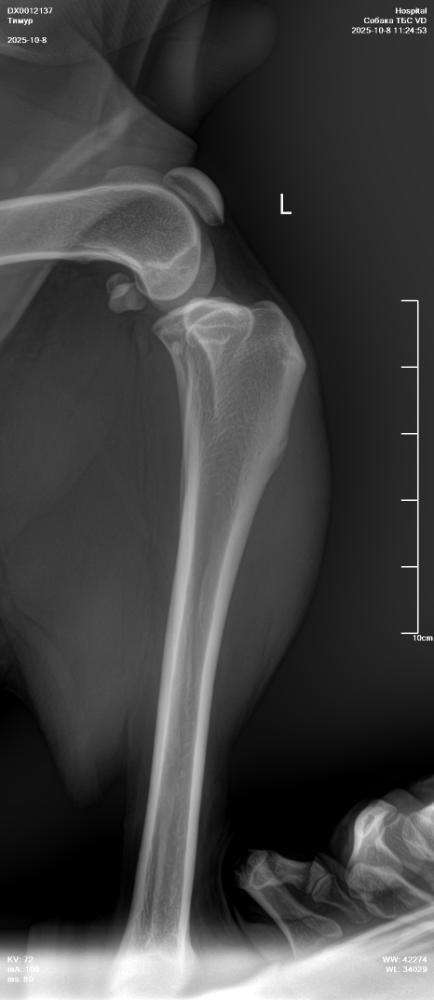

NataP Опубликовано 8 октября, 2025 Опубликовано 8 октября, 2025 Здравствуйте. Три дня назад после прогулки Тимур захромал, хотя сильных нагрузок не даём, немного поиграли с пуллером. Сегодня създили в клинику, сделали снимки без седации, кое как смогли завалить, сопротивлялся, поэтому снимки получились не такие, как хотелось бы. Но даже по ним нам ставят дисплазию и рекомендуют операцию по протезированию. Хочу проконсультироваться онлайн в Москве. Посоветуйте, пожалуйста, где сейчас лучше консультироваться, и подойдут ли такие снимки, или лучше переделать под седацией. Сейчас пока выписали онсиор или робексеру на 10 дней, но Омез сказали, давать не нужно, а я сомневаюсь, может всё-таки давать? Простите за много букв, просто в панике пока, а кроме вас не к кому обратиться. Снимки прикрепила.

Кирюша и Маруся Опубликовано 9 октября, 2025 Опубликовано 9 октября, 2025 Снимки без седации полная дезинформация. А к врачам, которые делают их для постановки диагноза лучше не ходить. Сделайте нормальные снимки с седацией у профи. При сомнении и пон азначению врача - МРТ. А обезбол крупной моложой собаке на травированную связку - это странно, так как нужно граничивать движение, а не просто снимать болевой и давать скакать. По врачам в МСК: Мезин, Еремин, Ягников, Воронцов, Самошкин, Середа, Давыдов, Гранин... Выбирайте любого. Нормальные рентгены делают они все. 1

NataP Опубликовано 9 октября, 2025 Автор Опубликовано 9 октября, 2025 То есть эти снимки вообще безполезны? Зря только с Тимуром воевали, чтоб на стол уложить(

Звезда Севера Опубликовано 9 октября, 2025 Опубликовано 9 октября, 2025 К сожалению, да. Такие снимки не информативны. Я так понимаю, что вам ближе в Нижний Новгород ехать? Может, там найти хороших специалистов?